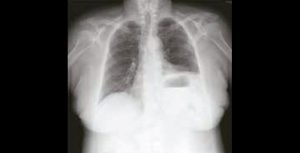

La dyspnée chez la personne âgée : apprendre à la définir

La prise en charge d’une dyspnée chez la personne âgée nécessite une analyse sémiologique précise en connaissant les spécificités inhérentes au grand âge. La radiographie thoracique reste incontournable, même si l’iconographie en coupe tend à…